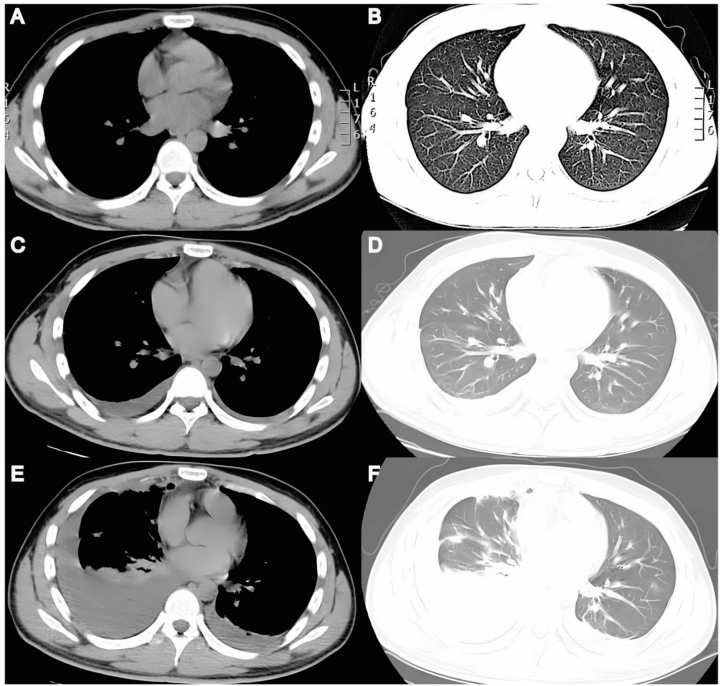

本文报道一例21岁男性在胸腔镜交感神经切断术(TS)治疗原发性多汗症(PH)后出现罕见双侧胸腔积液并发症。研究团队通过胸腔穿刺术和Light's标准确诊为渗出性积液,排除了结核、肿瘤及乳糜胸可能,提出血管通透性增加和淋巴回流障碍的病理机制,为TS术后罕见并发症的诊断与管理提供了重要临床参考。